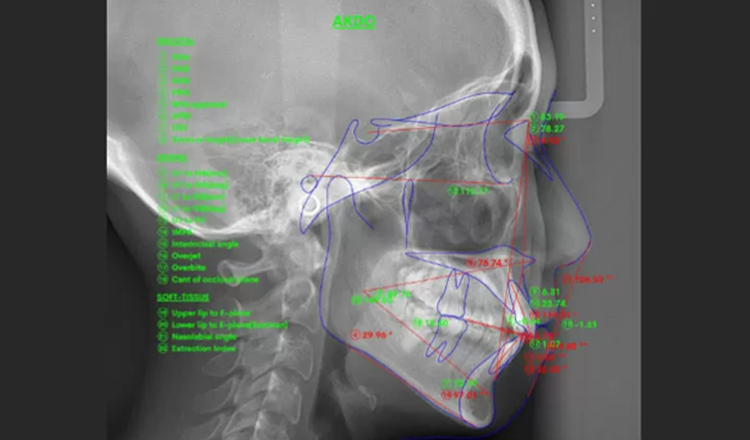

矯正治療を成功に導くには、歯科医師の経験と技術はもちろん、歯科用CTやセファログラム(頭部X線)、口腔内スキャナーなど、精密な診断と治療計画に必要な設備も欠かせません。

精密なデジタル診断を実施

当院では、口腔内スキャナーや3D画像解析、AIによる分析などの先進のデジタル技術を駆使して、正確でブレのない診断を行っています。精密なデータに基づく治療計画を立てていきます。

歯並びだけでなく、お顔全体の骨格や筋肉の動きまで考慮し、自然で美しいバランスを追求しています。横顔のEラインや表情の調和を重視し、機能性と審美性を兼ね備えた治療をご提供します。